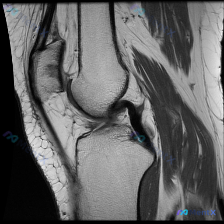

刚整理了一个很有临床意义的病例,核心矛盾是「临床怀疑软骨异常,但现有影像完全正常」,把整个分析思路分享给大家。 病例基础信息 这是一份单张膝关节矢状位T1加权MRI影像,临床提出的核心观察方向是「软骨异常」,无其他临床病史、症状或其他检查资料。 影像具体观察结果 我们先把影像所见说清楚: 1. 骨骼...